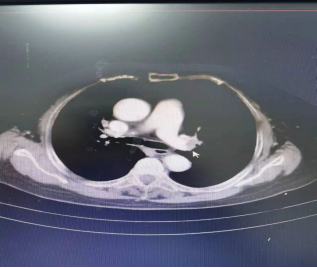

83岁高龄的刘奶奶,因腹痛、恶心、呕吐整整一天不见好转,便来到河豚直播体育app就诊。肝胆血管外科王启伦主任、重医附二医院血管外科付健医生通过详细询问病史,结合检查、查体情况后考虑是肠系膜上动脉栓塞可能,需血管造影明确情况。一切准备就绪,肝胆血管外科医疗团队在介入手术中心的配合下即刻为刘奶奶行腹主动脉+右侧髂骨动脉+肠系膜上动脉造影术,术中证实肠系膜上动脉栓塞。再次与家属沟通签字,为刘奶奶行肠系膜上动脉吸栓、溶栓治疗,手术很成功,术后刘奶奶腹痛即刻消失。

患者手术前后造影对比图: